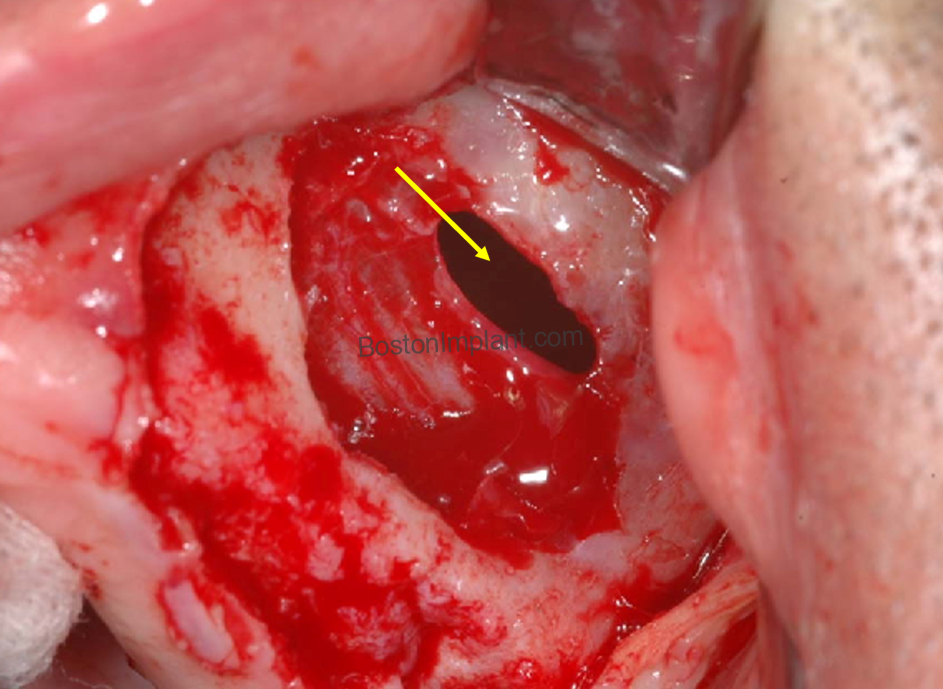

3. Surgical Hemorrhage (Bleeding Control)

The lateral wall of the sinus contains small blood vessels that must be navigated carefully during the creation of the surgical window.

• The Risk: Approximately 10% of patients have larger vessels in this area that could cause significant bleeding if not identified during planning.

• Prevention & Clinical Protocol: Through “Vessel Mapping” via 3D CBCT imaging, Dr. Lee identifies the exact location of these vessels and plans the surgical access to bypass them entirely.